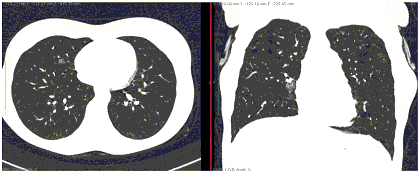

2. Наличие клинических проявлений, указанных в п. 1, в сочетании с характерными изменениями в легких по данным компьютерной томографии (КТ) (см. Приложение 1 настоящих рекомендаций) вне зависимости от результатов однократного лабораторного исследования на наличие РНК SARS-CoV-2 и эпидемиологического анамнеза.

- Изменения при КТ (рентгенографии), типичные для вирусного поражения (объем поражения минимальный или средний; КТ 1-2)

- Изменения в легких при КТ (рентгенографии), типичные для вирусного поражения (объем поражения значительный или субтотальный; КТ 3-4)

- Изменения в легких при КТ (рентгенографии), типичные для вирусного поражения критической степени (объем поражения значительный или субтотальный; КТ 4) или картина ОРДС.

КТ имеет высокую чувствительность в выявлении изменений в легких, характерных для COVID-19. Применение КТ целесообразно для первичной оценки состояния ОГК у пациентов с тяжелыми прогрессирующими формами заболевания, а также для дифференциальной диагностики выявленных изменений и оценки динамики процесса. КТ позволяет выявить характерные изменения в легких у пациентов с COVID-19 еще до появления положительных лабораторных тестов на инфекцию с помощью МАНК. В то же время, КТ выявляет изменения легких у значительного числа пациентов с бессимптомной и легкой формами заболевания, которым не требуется госпитализация. Результаты КТ в этих случаях не влияют на тактику лечения и прогноз заболевания при наличии лабораторного подтверждения COVID-19. Поэтому массовое применение КТ для скрининга асимптомных и легких форм болезни не рекомендуется.

15. Рекомендации по формированию описаний и оценке изменений в легких и ОГК при имеющейся/подозреваемой пневмонии COVID-19 представлены в Приложении 1.